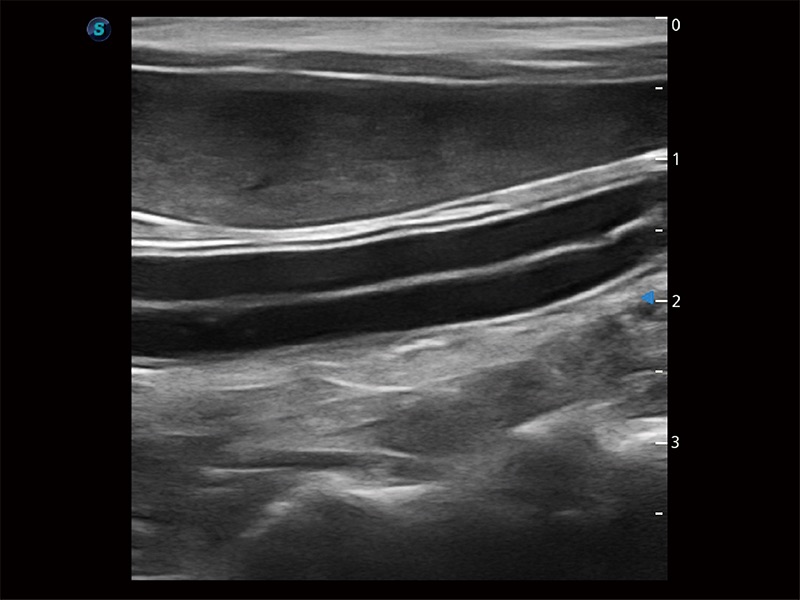

高性能和先進(jìn)的臨床應(yīng)用工具可以為動(dòng)物醫(yī)生提供臨床信心。ProPet 80 搭載了先進(jìn)的腹部和淺表應(yīng)用工具,幫助醫(yī)生在日常臨床實(shí)踐中發(fā)揮前所未有的作用。

為精細(xì)結(jié)構(gòu)及組織邊緣提供高清晰度的圖像和更大的成像視野。幫助減輕醫(yī)生的用眼疲勞,快速精準(zhǔn)獲得測(cè)量的數(shù)據(jù)。